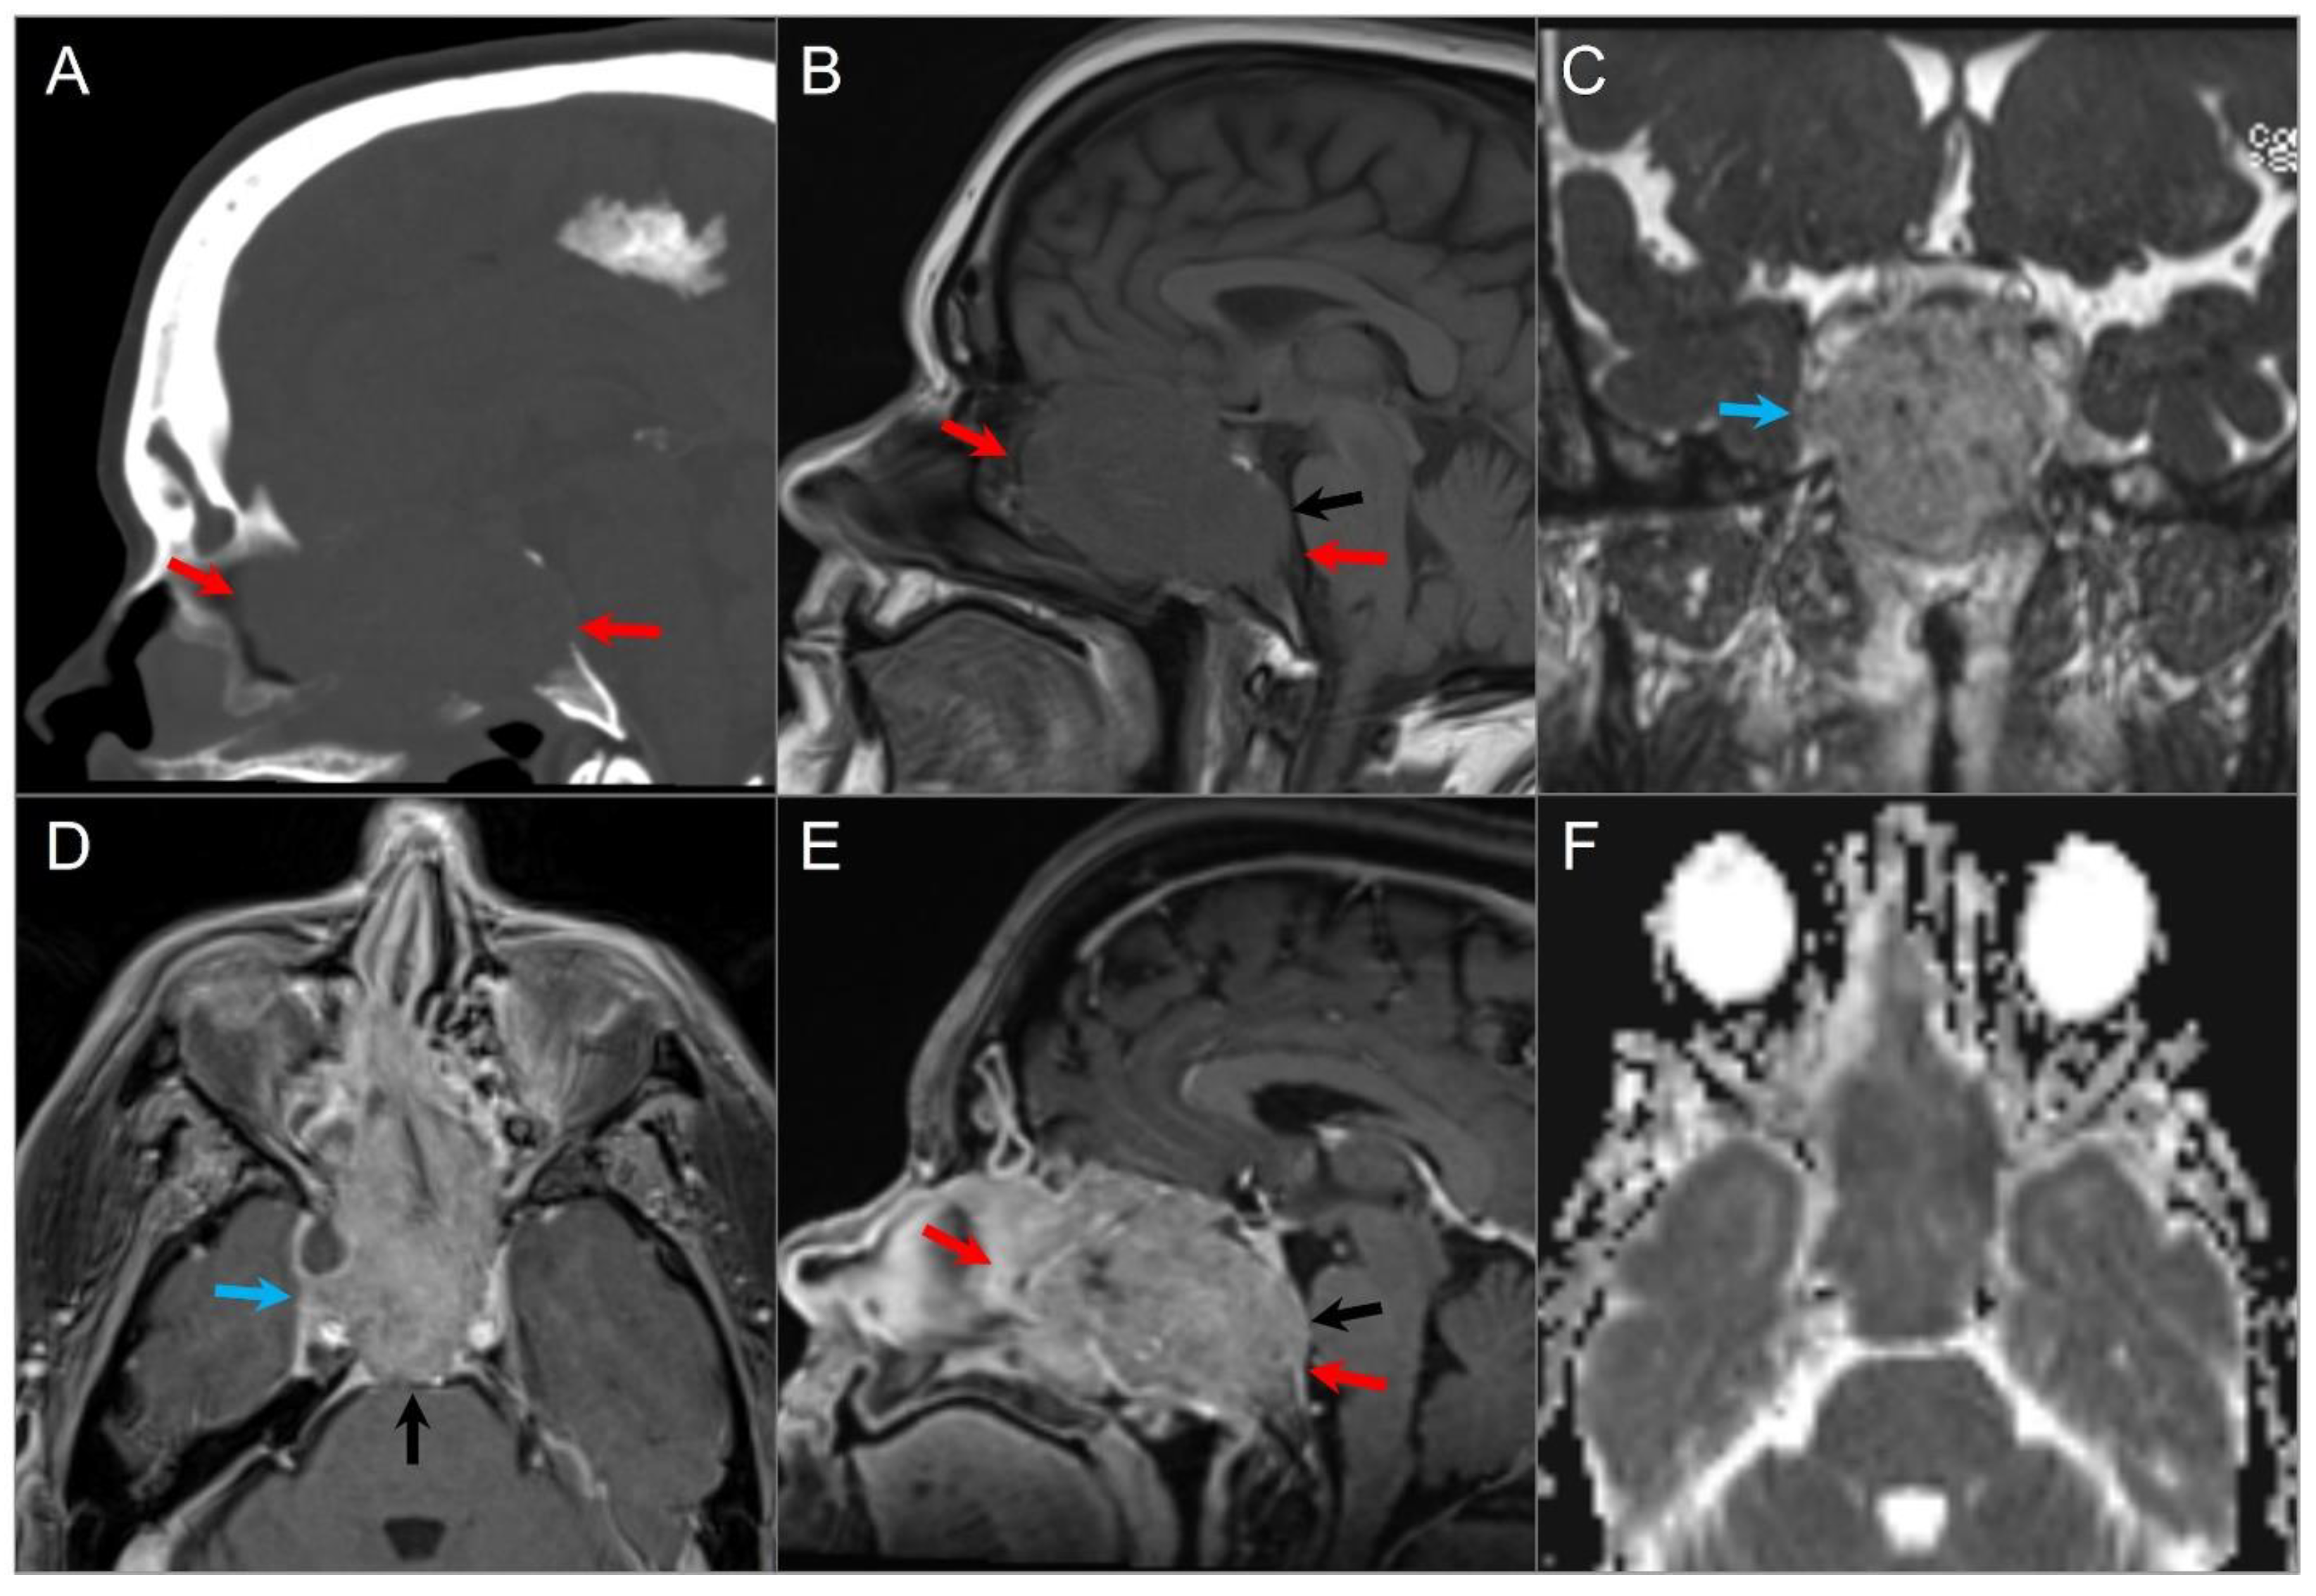

4.4.1. Chordoma

5.10. Ecchordosis Physaliphora

5.11. Giant Aneurysm